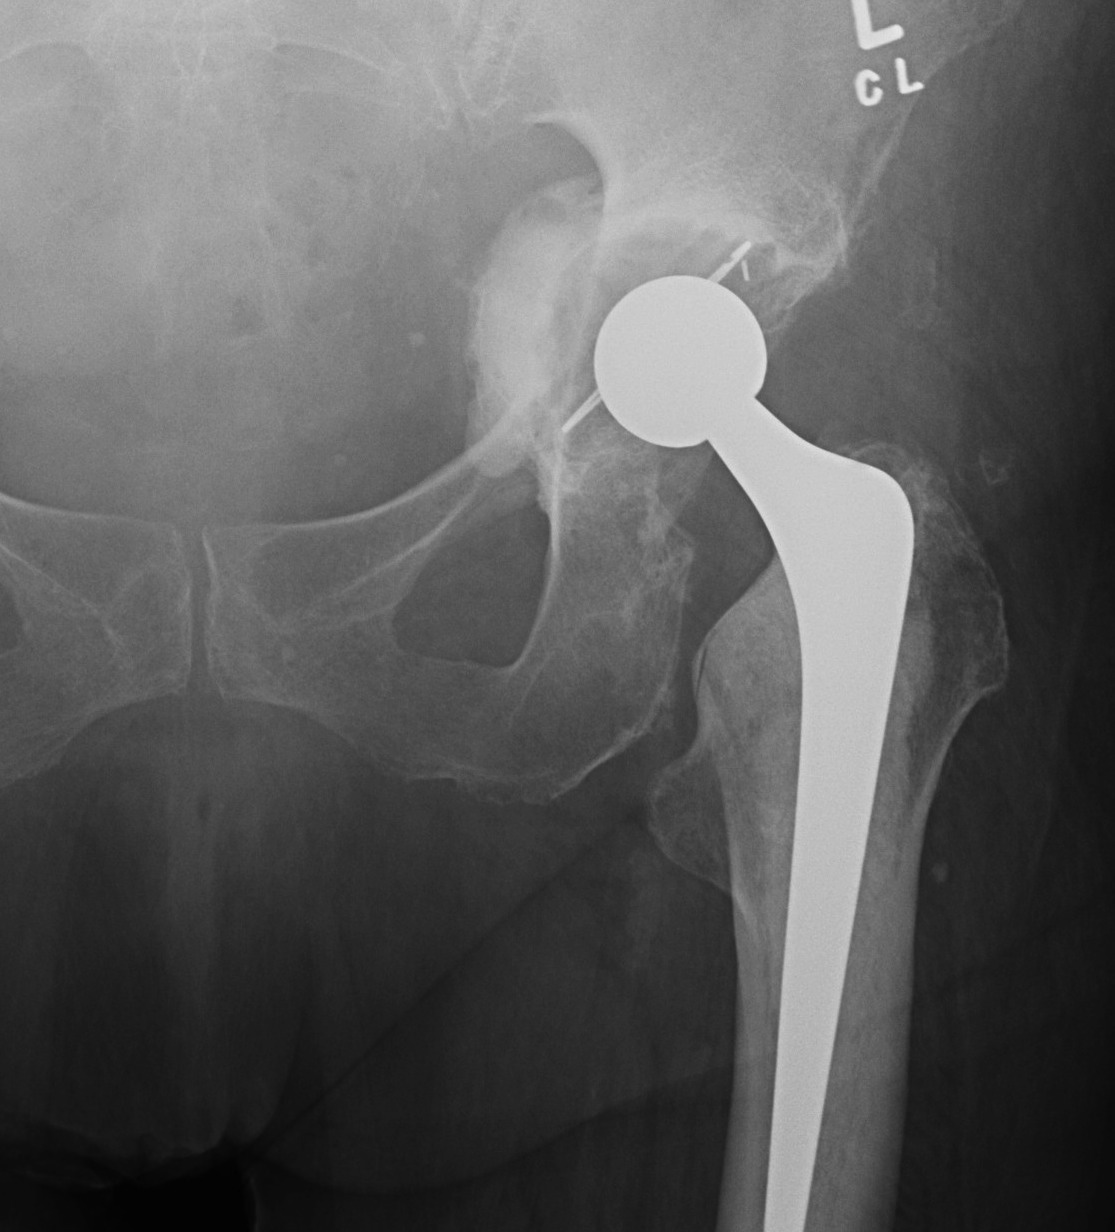

Anterior retractors / dissection

Anterior quadrant screws and drills